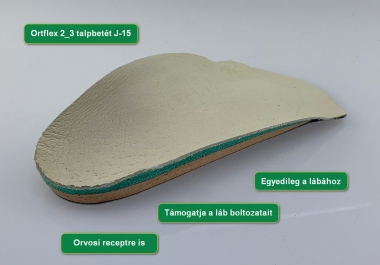

- a láb statikai hibája is korrigálva lesz a lábhoz és a cipőhöz készített rugalmas talpbetéttel

Talpbetéteink